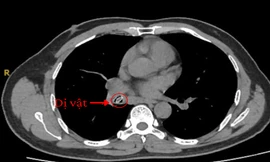

Ho triền miên suốt một năm vì hạt trái cây 'đi lạc' trong phổi

TPO - Suốt một năm qua, người đàn ông phải sống chung với những cơn ho kéo dài tưởng chừng do bệnh hô hấp mạn tính. Không ngờ, “thủ phạm” thực sự lại là một hạt sapoche kẹt sâu trong phế quản.